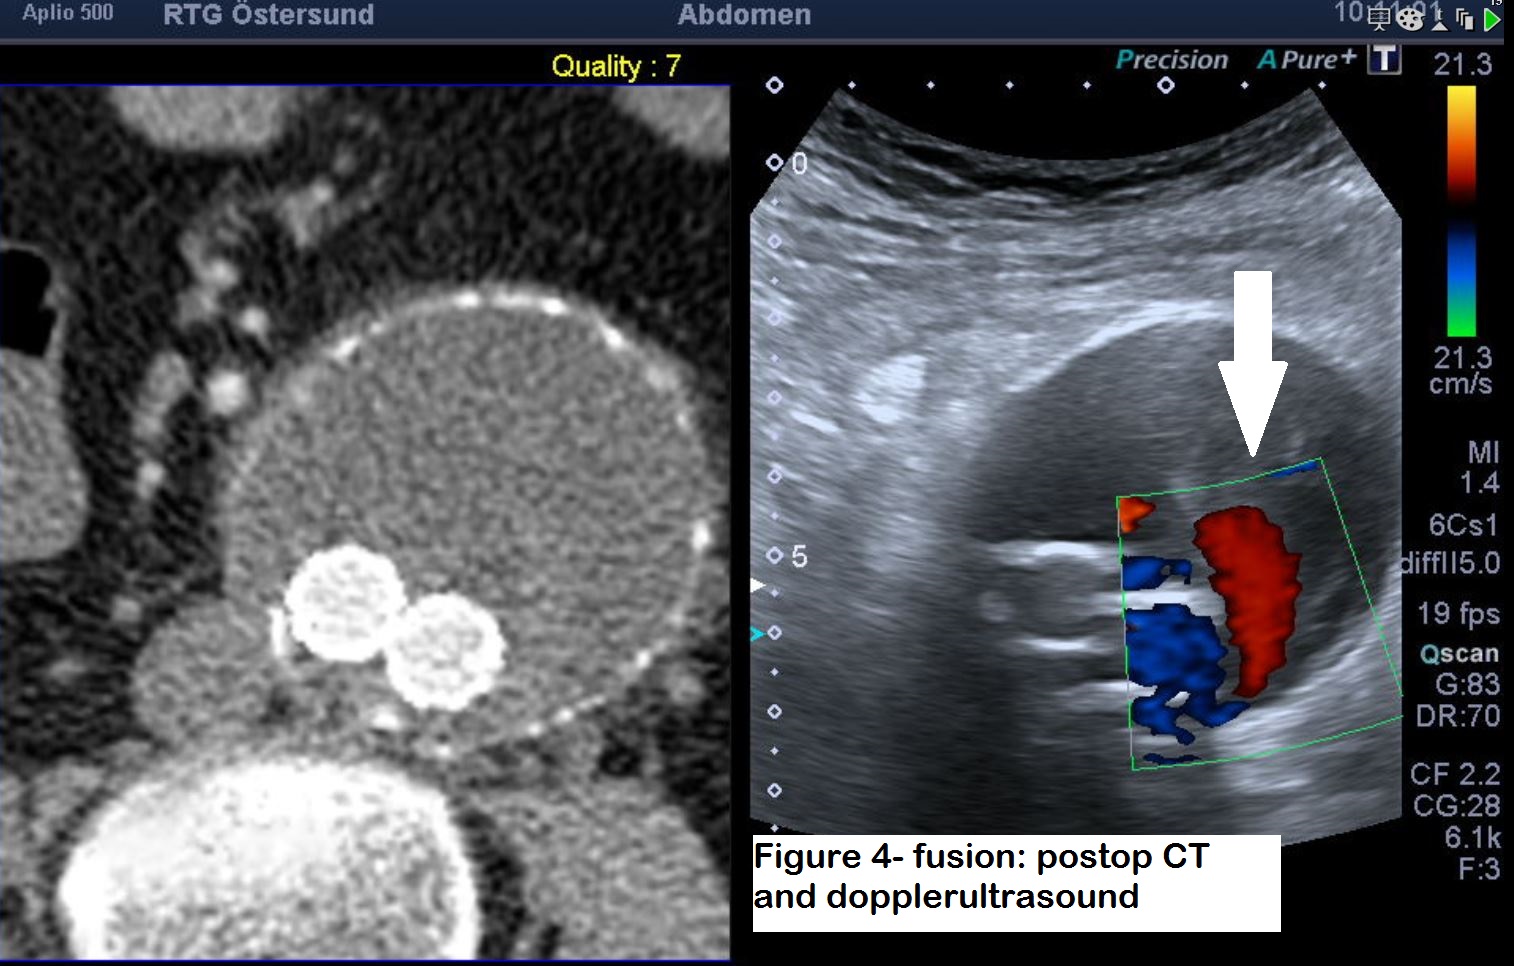

Figure 4: Ultrasound fusion with the postop CT to better delineate the anatomy. This would also provide more anatomical information to the vascular surgeon and interventional radiologist for future intervention. The Doppler shows very clear colour flow signal within the sac, where it is apparent that it is a type 2 leak arising from the lumbar arteries.